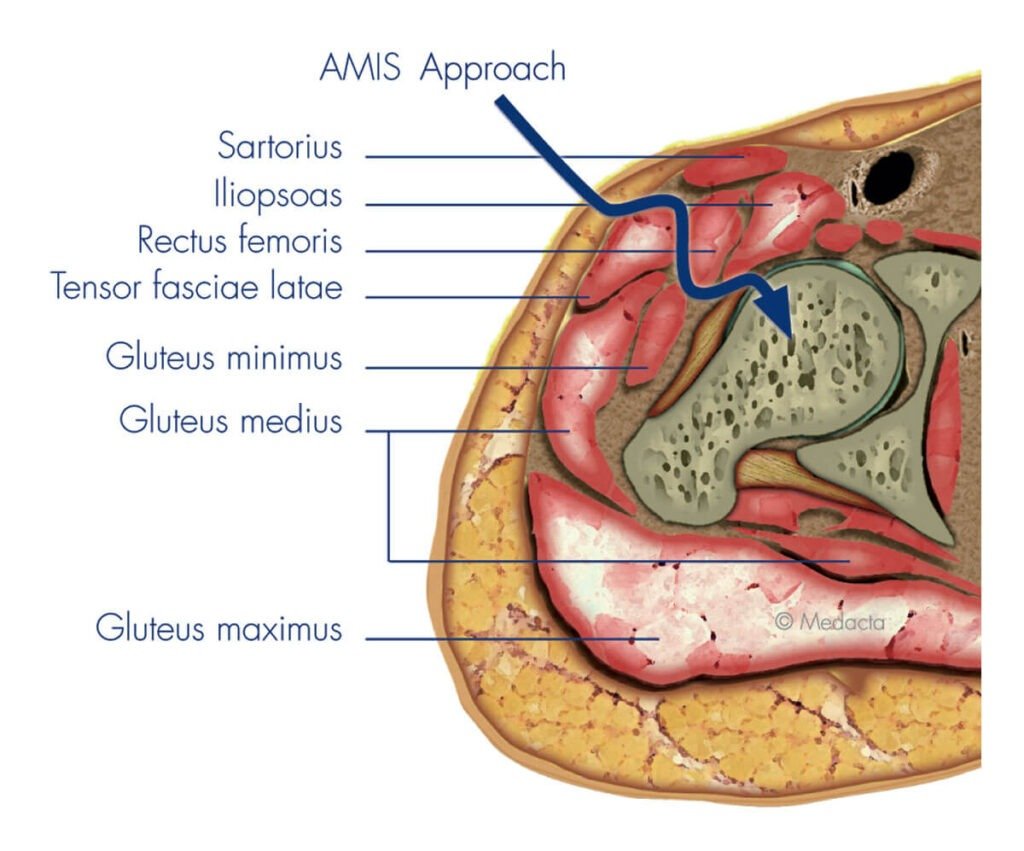

Hip replacement surgery can be performed using several different surgical approaches. The way the hip joint is accessed, known as the surgical approach, can influence muscle preservation, recovery, and the positioning of the prosthetic components. There is no single “best” technique for every patient; the most appropriate approach depends on your anatomy, joint condition, medical history, and individual recovery goals.

Dr Hockings is experienced in multiple approaches, including the anterior approach, posterior approach, and bikini incision techniques. Each method provides specific advantages in terms of exposure, soft tissue handling, and incision placement.

Dr Hockings frequently performs total hip replacement using the anterior approach, which allows access to the joint from the front of the hip. This technique follows a natural path between muscles rather than cutting through them, which may result in less soft tissue trauma during surgery.

Potential benefits of the anterior approach may include:

- A smaller surgical incision at the front of the hip

- Earlier mobilisation and walking after surgery

- Reduced disruption to muscles and tendons

- Lower early dislocation risk in some cases

Dr Hockings has undertaken post-fellowship training in anterior hip replacement and uses this method when it is safe and appropriate for the patient. In suitable cases, it can also be performed using a bikini incision, which follows the natural line of the groin crease.